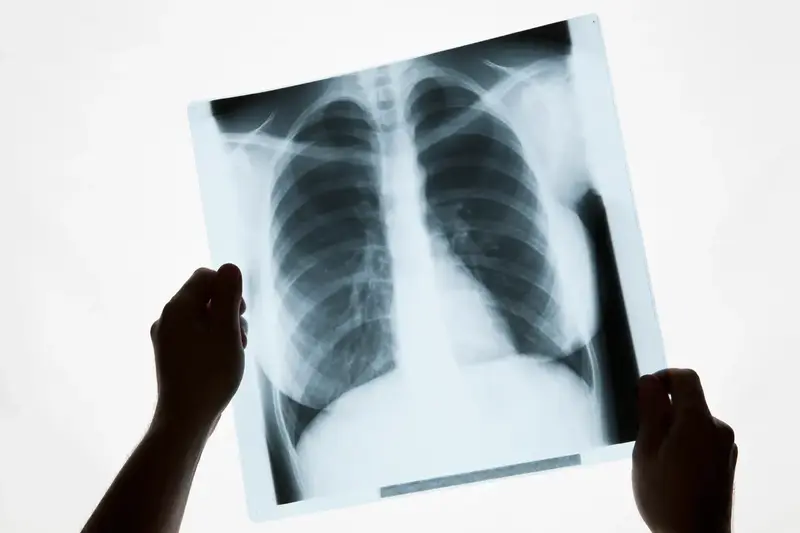

It's true that a chest X-ray (also called a chest radiograph) is often the first gateway to detecting a potential enlargement of the heart, known medically as cardiomegaly. However, it is crucial to understand that this X-ray result is not a final diagnosis but rather a very valuable initial clue. It serves as a signal for the doctor to conduct a more thorough investigation.

A chest X-ray is a quick, non-invasive, and widely available screening test. During the X-ray, the doctor analyzes the heart's silhouette or shadow. One simple metric used is the Cardiothoracic Ratio (CTR). This is a comparison between the horizontal width of the heart and the internal width of the chest cavity (thorax). If this ratio is greater than 0.5 (or 50%), it indicates the presence of an enlarged heart on the X-ray.

Although very useful as an initial marker, it is important to be aware of the limitations of an X-ray:

- Two-Dimensional Image: An X-ray only provides a two-dimensional shadow. It cannot distinguish between an enlargement of the heart muscle (hypertrophy) and the presence of fluid in the sac surrounding the heart (pericardial effusion), both of which can make the heart's silhouette appear larger.

- Does Not Assess Function: An X-ray provides absolutely no information about the heart's pumping function, the condition of the valves, or blood flow.

- Technical Variability: The results can vary slightly depending on the patient's position and the degree of inspiration (how deeply they breathe in) when the image is taken.

So, if you receive a result showing an enlarged heart on an X-ray, do not panic. Consider it a yellow flag, an important signal to proceed to the next stage of examination.